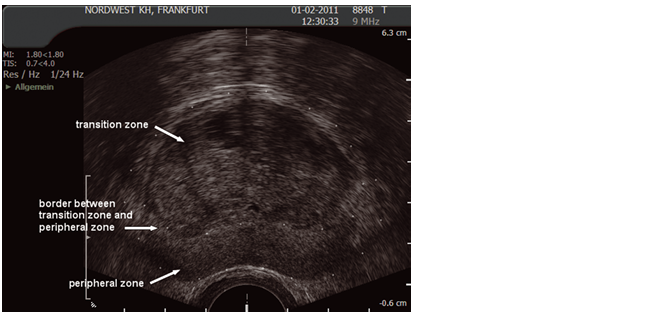

4.2 Zonal anatomy

Three glandular regions can be identified in the prostate: central, peripheral and transition zones. There is a further non-glandular area called the anterior fibromuscular stroma.

The peripheral zone accounts for 75% of the prostate tissue in young men but the transition zone increases in size with ageing due to benign prostate enlargement (BPE), while the central zone atrophies and the peripheral zone stays static. Thus, for clinical purposes the important regions are the peripheral and transition zones.

It is the peripheral zone in which the majority of prostate cancers occur, whereas BPE arises in the transition zone.

Fig. 5 Ultrasound image of transition and peripheral zone

(Courtesy of: S. Hieronymi)